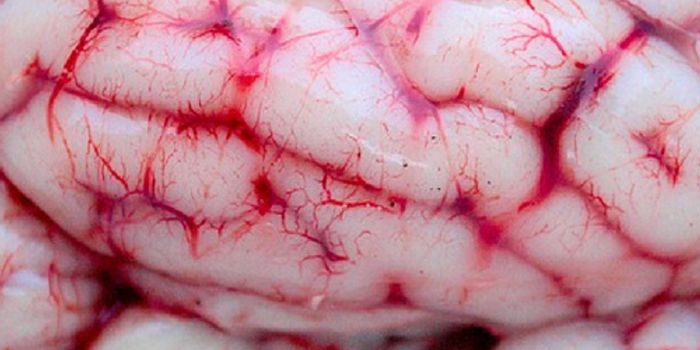

MAY 05, 2016VideosThe brain has about 100 billions of neurons and at least 100 trillion neuron connections. These cells and connections ma ...

MAR 17, 2015Videos‘The Brain Prize' is awarded to one or more scientists who have distinguished themselves by an outstanding contribution ...

NOV 13, 2017VideosAfter his death by suicide, former NFL player Aaron Herandez's family announced that his brain would be donated to the C ...